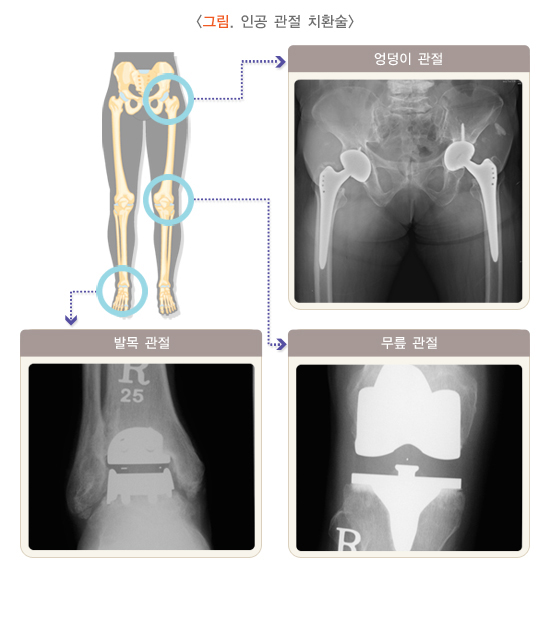

수술적 치료로 관절경 수술법은 비교적 간단한 시술로 증상 완화를 기대할 수 있으나, 효과의 지속 여부가 일정하지 않습니다. 대표적인 수술 방법인 인공관절 치환술은 통증을 효과적으로 줄이고, 변형된 관절이 교정되는 효과가 있습니다. 그러나 인공관절의 수명이 제한적이므로 향후 재수술이 필요할 수 있고, 수술 중 출혈이나 감염 등 합병증이 발생할 수 있으므로 충분히 상의해서 결정해야 합니다.

(4) 관절 성형술(치환술)

관절 성형술은 심한 관절염에서 고려되는 방법으로 인공관절 치환술이 대표적입니다. 수술 전 가장 기본적으로 고려해야 할 조건은 질병의 심한 정도, 나이, 활동량입니다. 50세 미만으로 젊은 환자는 인공관절 외의 다른 수술법을 먼저 고려하며, 나이가 많고 증상이 심하다고 해도 무릎 관절에 감염이 생긴 경우(골수염, 화농성 관절염 등), 조절되지 않는 심장병, 진행된 간경화, 무릎 이외 부위에 세균성 감염이 있는 경우(요로감염, 폐렴 등)에는 수술을 피하거나 연기해야 합니다.

수술적 치료는 원래 관절을 살리는 방법과 관절을 대치하는 방법이 있습니다. 원래 관절을 살리는 방법으로 골극 절제 및 낭종 소파술, 근유리술, 대퇴 근위부 절골술, 골반 절골술 등이 있습니다. 인공관절 치환술은 원래의 관절을 인공관절로 대치하는 방법입니다. 골관절염의 경우 비구와 대퇴골두가 동시에 손상되므로 엉덩이 관절 전체를 바꾸는 전치환술이 가장 보편적으로 이용됩니다.

심한 통증이 지속되거나 관절의 불안정, 변형, 운동 제한이 진행하면 수술적으로 치료합니다. 수술적 치료는 관절경 세척술 및 변연 절제술, 골연골 이식술, 자가 연골 이식술, 절골술, 인공관절 치환술 등 다양한 방법이 있으며, 인공관절 치환술도 한 구획 치환술과 전치환술이 있습니다. 연령과 기대 활동 수준, 골관절염의 정도, 관절염이 진행된 무릎 관절 구획 수에 따라 구체적인 치료 방법을 선택합니다.